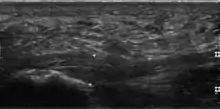

يعتمدُ تشخيص التهاب اللفافة الأخمصية على عددٍ من العلامات والأعراض، كما أنَّ التصوير بالموجات فوق الصوتية قد يُساعد أحيانًا.[1] تُوجد حالاتٌ أخرى لديها أعراضٌ مشابهة وتتضمن الفصال العظمي، والتهاب الفقار القسطي، ومتلازمة وسادة العقب، والتهاب المفاصل التفاعلي.[5][6]

تحتوي اللفافة الأخمصية طبيعيًا على ثلاث حزمٍ، حيثُ يبلغ سُمك الحزمة المركزية 4 ملم، والحزمة الجانبية 2 ملم، أما الحزمة الوسطية تكون أقل من 1 مل.[23] نظريًا، تزداد احتمالية حدوث التهاب اللفافة بزيادة سُمك اللفافة الأخمصية عند المنغرس العَقِبي، حيثُ أنَّ السُمك أكثر 4.5 ملم يُعتبر مفيدًا إلى حدٍ ما في التصوير بالموجات فوق الصوتية، وسُمك 4 ملم في التصوير بالرنين المغناطيسي،[24] ولكن على الرغم من كلِ هذا، إلا أنَّ نتائج التصوير الطبي مثل زيادة سُمك اللفافة الأخمصية، قد تكون غير موجودةٍ في الأفراد المُصابين بالالتهاب أو موجودة في أفرادٍ لا تظهر لديهم أي أعراضٍ للمرض، وبالتالي فإنَّ فائدة نتائج التصوير الطبي محدودة.[18]